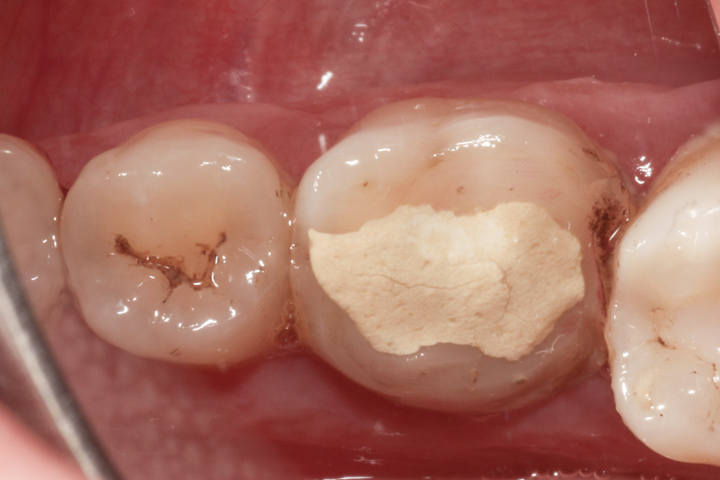

PRZYKŁAD 3